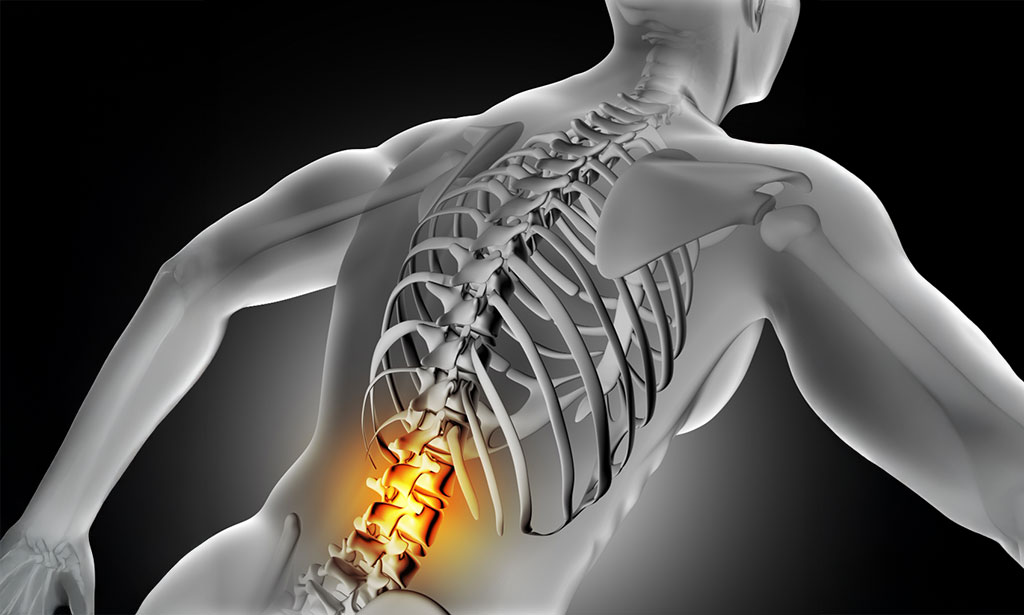

Low Back Pain Chiropractic Care